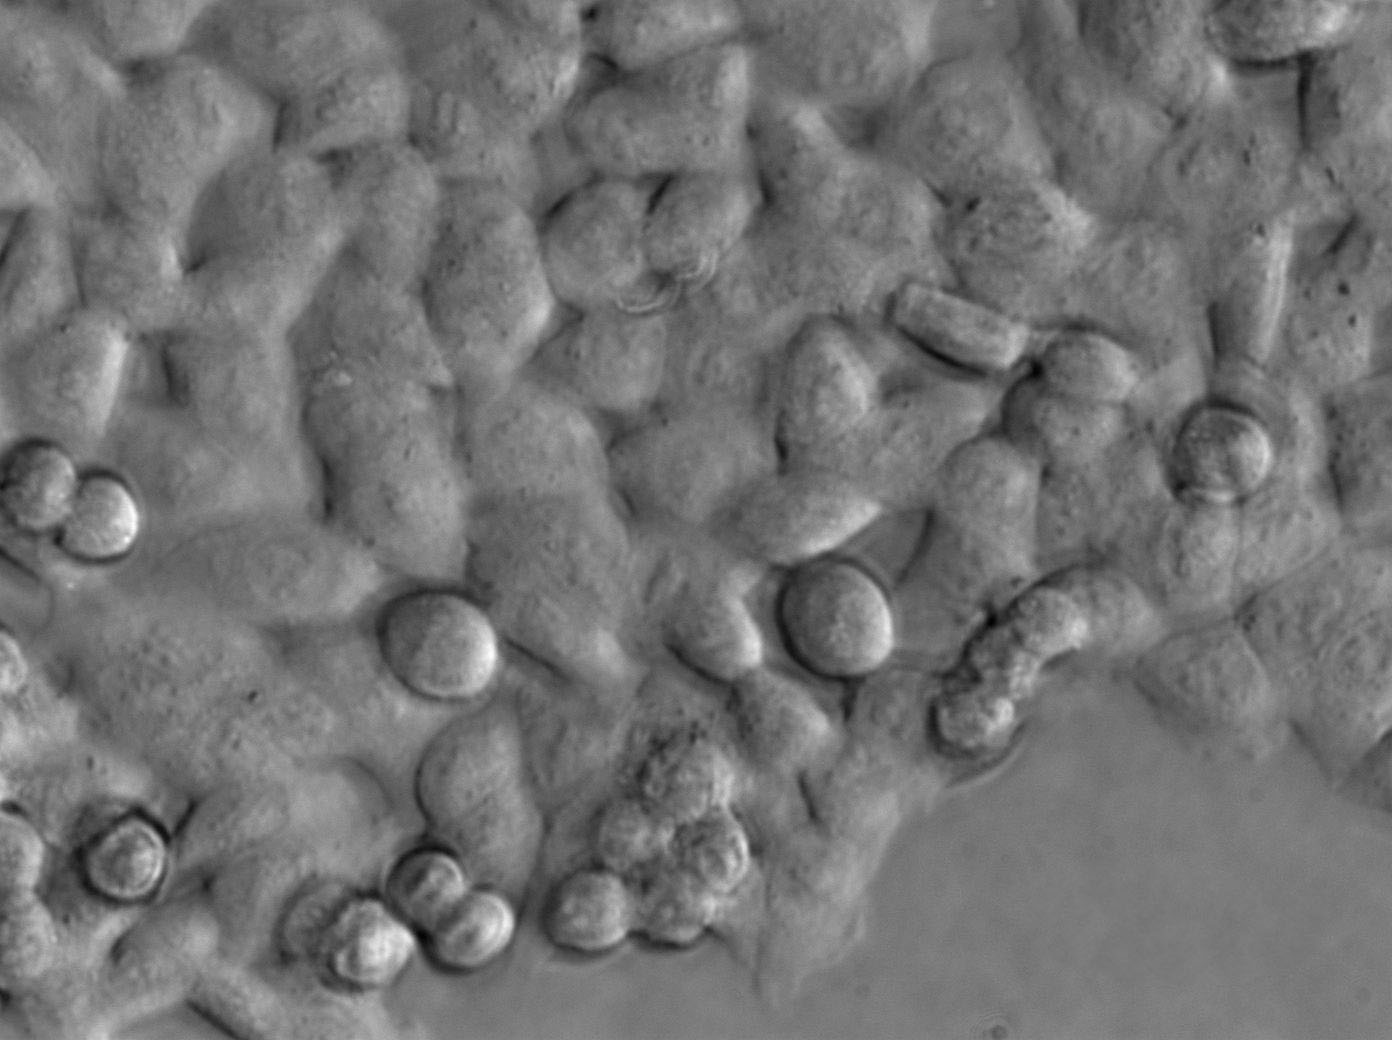

UM-UC-1 Cells|人膀胱移行癌克隆细胞

细胞形态:上皮细胞样

细胞生长:贴壁